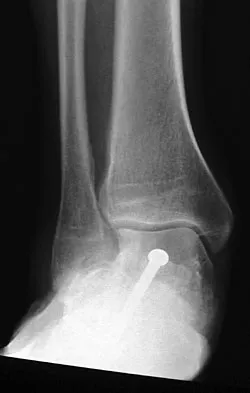

Figures 4a through 4c show the radiographs of a 43-year-old woman who sustained a twisting injury to her right ankle. She has ankle pain and tenderness medially and laterally. To help determine the optimal treatment, an external rotation stress radiograph of the ankle is obtained. This test is designed to evaluate the integrity of what structure?

Explanation

In the presence of a supination external rotation-type fracture of the distal fibula (Weber type B), stability of the ankle is best assessed by performing an external rotation stress AP view of the ankle. This test is used to assess the integrity of the deltoid ligament. The presence of a deltoid ligament rupture results in instability and generally is best managed surgically. The gravity stress test can also be used. Egol KA, Amirtharajah M, Tejwani NC, et al: Ankle stress test for predicting the need for surgical fixation of isolated fibular fractures. J Bone Joint Surg Am 2004;86:2393-2398. McConnell T, Creevy W, Tornetta P III: Stress examination of supination external rotation-type fibular fractures. J Bone Joint Surg Am 2004;86:2171-2178.